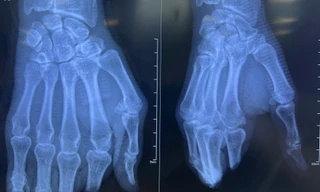

lx.jpg

Phòng chẩn trị y học cổ truyền Hoàng Minh Đường thuộc Công ty TNHH Hoàng Minh Đường ở phố 1 Lâm Xa, xã Bá Thước.